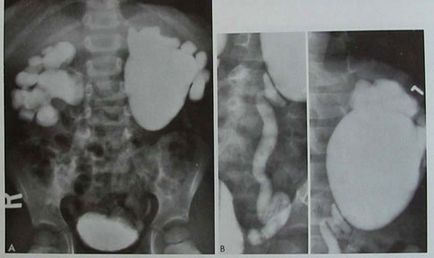

5. ábra. A. kiválasztó urográfia feltárta egy fiú 4 éves visszatérő hasi fájdalom és a hőmérséklet emelkedik, a kétoldalú hydronephrosist.

A kiválasztó urograms ha hidronefrózis jelölve expanziós medence és a csészék, nem kontrasztos ureter, vagy meghatározott disztális jele nélkül expanziós átmérőjű. Maximalizálása gyűjtőrendszer vese mérete megfigyelhető a késői vagy késleltetett képek (40 perc, 90 perc. 3 óra.). Laziksnaya minta háttérben kiválasztó urográfia használják megerősíteni a diagnózist főleg idősebb gyermekek (N.A.Lopatkin, A.G.Pugachev (1984) módszerei ebben a vizsgálatban a következő :. A gyermek korábban bőséges poitsya (hidratáció), a húgyhólyag kiürítésének először. forrás kép végezzük 15 percig. a beadás után a kontrasztanyag (a standard dózisai kor). További Lasix intravénásán az arány (1 mg / kg). 3. végezzük a képre. 1 perc, 5 perc., és 10 perc. beadása után Lasix. elzáródás tüneteit úgy növekszik a medence mérete és csészék 30%, szemben a kezdeti méret (15 min.).